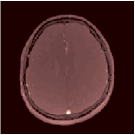

VI-E In-vivo experiments

Two sets of experiments were conducted here: first, we used the 2D and 3D acquisition sequences for scanning a healthy volunteer’s brain (real-world acquisitions). Figures 6 and 7 display the parametric maps reconstructed from 2D spiral and radial readouts. We computed the T1, T2 and proton density (PD) maps using baseline reconstruction algorithms ZF, VS, LR, FLOR, AIR-MRF and our proposed LRTV. While baselines use DM either for quantitative inference or also during reconstruction (i.e. AIR-MRF), we further compare the DM-free LRTV’s performance when cascaded to DM, KM and MRFResnet for quantitative inference. For the 3D spiral acquisitions we compared LRTV and its closest competitor VS in Figure 8. Outcomes from other tested algorithm are displayed in the supplementary materials (Figure S5). Since FLOR does not use dimensionality-reduction, our system ran out of memory during 3D reconstruction; hence results are not reported in this case.

VI-E1 Discussion

The LRTV-DM and LRTV-MRFResnet perform on par, and both outperform all tested baselines for reconstructing T1, T2 and PD maps in all acquisition schemes. This can be observed both visually in Figures 6, 7, 8, S2 and S3, and quantitatively in Table IV across all tested metrics. Other baselines were unable to successfully remove the under-sampling artefacts in TSMIs, and these errors propagated to the parameter inference phase and resulted in inaccurate maps. Temporal-only priors incorporated within LR are shown insufficient to regularise the inverse problem and LR sometimes (e.g. 2D spiral acquisitions) can admit solutions with even stronger artefacts than the model-free ZF baseline. This issue was previously studied for other non-Cartesian MRF readouts that similar to our spiral/radial trajectories, miss to sample the corners of the k-space in all timeframes (see section 2.2.2 and figure 2 in [19]). In the absence of reference for the k-space corners information, the LR iterations despite minimising the objective can converge to solutions with high-frequency artefacts, as visible in the computed maps. This highlights the need for adding an appropriate spatial-domain regularisation. FLOR reduces the LR’s artefacts but this improvement is limited because the suggested nuclear norm penalty does not incorporate an explicit spatial regularisation. Further for reducing artefacts, FLOR can introduce an undesirable bias in the computed T1/T2 maps e.g. see error maps in Figures S2 and S3. The non model-based VS baseline incorporates spatial regularisation and results in spatially smoother maps than ZF and LR, but it is unable to output artefact-free images. Further and consistent with our in-vitro experiment, we observe that VS overestimates the T2 values (e.g. in White and Grey matter regions) in tested 2D acquisitions i.e. the spatial regularisation trades off agains the quantification accuracy. The model-based AIR-MRF adds spatial regularisation through 2D/3D low-pass Gaussian filters however this trades off the sharpness of the computed maps and can increase the errors at the tissue boundaries (we searched Gaussian spreads that keep the blurs and high-frequency artefacts minimal). For our acquisition readouts, Gaussian filters performed better than disk filters of [19] for avoiding strong Gibbs artefacts. On the other hand, the spatiotemporally regularised LRTV greatly improves the TSMI reconstructions i.e. 4 dB enhancement compared to the closest competitor baseline (Table IV). This enables computing accurate and aliased-free multi-parametric inference using DM or the DM-free learning-based alternative MRFResnet as visible in Figures 6, 7, 8, S2 and S3. MRResnet and DM score competitive quantitative inference results i.e. T1 and T2 MAPE less than 5% and 9%, respectively (Table IV). KM also outputs comparably accurate T1 maps, however this shallow learning model despite having a model size larger than MRFResnet, is unable to learn accurate T2/PD quantification and it results in poor estimated maps, consistent with our observations in section VI-C.